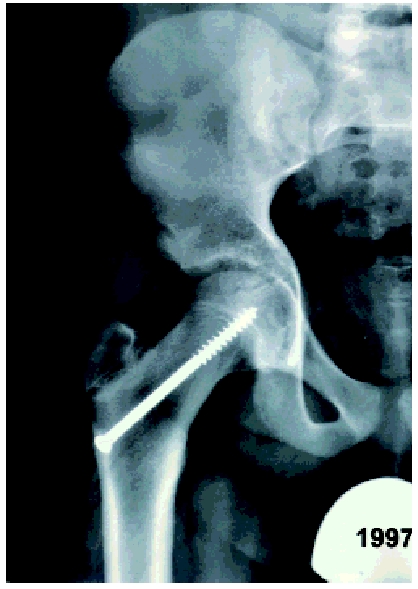

Marja van Wijk, een 12-jarig meisje met blanco voorgeschiedenis komt in augustus 2001 op het spreekuur orthopedie. Sinds oktober 2000 heeft ze last van haar linker heup na een val tijdens handbal. Ze blijft pijn in de heup en lies houden en heeft moeite met lopen. De huisarts schrijft Mensendieck-therapie voor. Drie maanden later wordt er een anteroposterior (AP) röntgenfoto van het bekken gemaakt. Deze wordt als niet-afwijkend beschreven, waarop de huisarts fysiotherapie voorschrijft. De klachten verbeteren tot ze in juni 2001 valt, waarna de klachten hevig verergeren. Het been is dan onbelastbaar; paracetamol helpt. Elf maanden na het ontstaan van de klachten komt ze op het spreekuur orthopedie. De klachten zijn afgenomen, maar ze loopt mank, heeft moeite om na het opstaan op gang te komen en kan maximaal een halfuur lopen. Ze heeft nog geen menarche gehad. Uit lichamelijk onderzoek blijkt dat ze een antalgisch looppatroon heeft met het linker been in exorotatie. De linker heup heeft een passieve flexie van 90° met een positieve Drehman (exorotatie bij flexie) en een opgeheven endorotatie. De functie van de rechter heup is niet afwijkend. Bij röntgenonderzoek van het bekken is zowel op de AP-opname als op de Lauenstein-opname (heup in 90° flexie en maximale abductie) links een ECF zichtbaar ( figuur 1). Deze blijkt achteraf ook op de foto van januari 2001 te zien. Vergeleken met de opname van toen is de afglijding toegenomen.

Beide patiënten werden acuut opgenomen en kregen een loopverbod. Ze werden de volgende dag geopereerd. De operatie bestond uit epifysiodese (fixatie in situ van de femurkop met een gecannuleerde schroef). Marja werd links en Anouk beiderzijds geopereerd. Bij controle na zes weken bleken de twee meisjes geen pijnklachten meer te hebben. Dat het te laat stellen van de diagnose ernstige gevolgen kan hebben, illustreert de volgende casus.